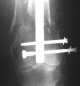

Attached are few examples from our Hospital:

B. Fixation loosening: distal cutting of the nail, non-unions do happen (cases attached).

Locking Plating has more distal screws than any nail, fixed angles and provides much better fixation, especially in osteoporotic bone.